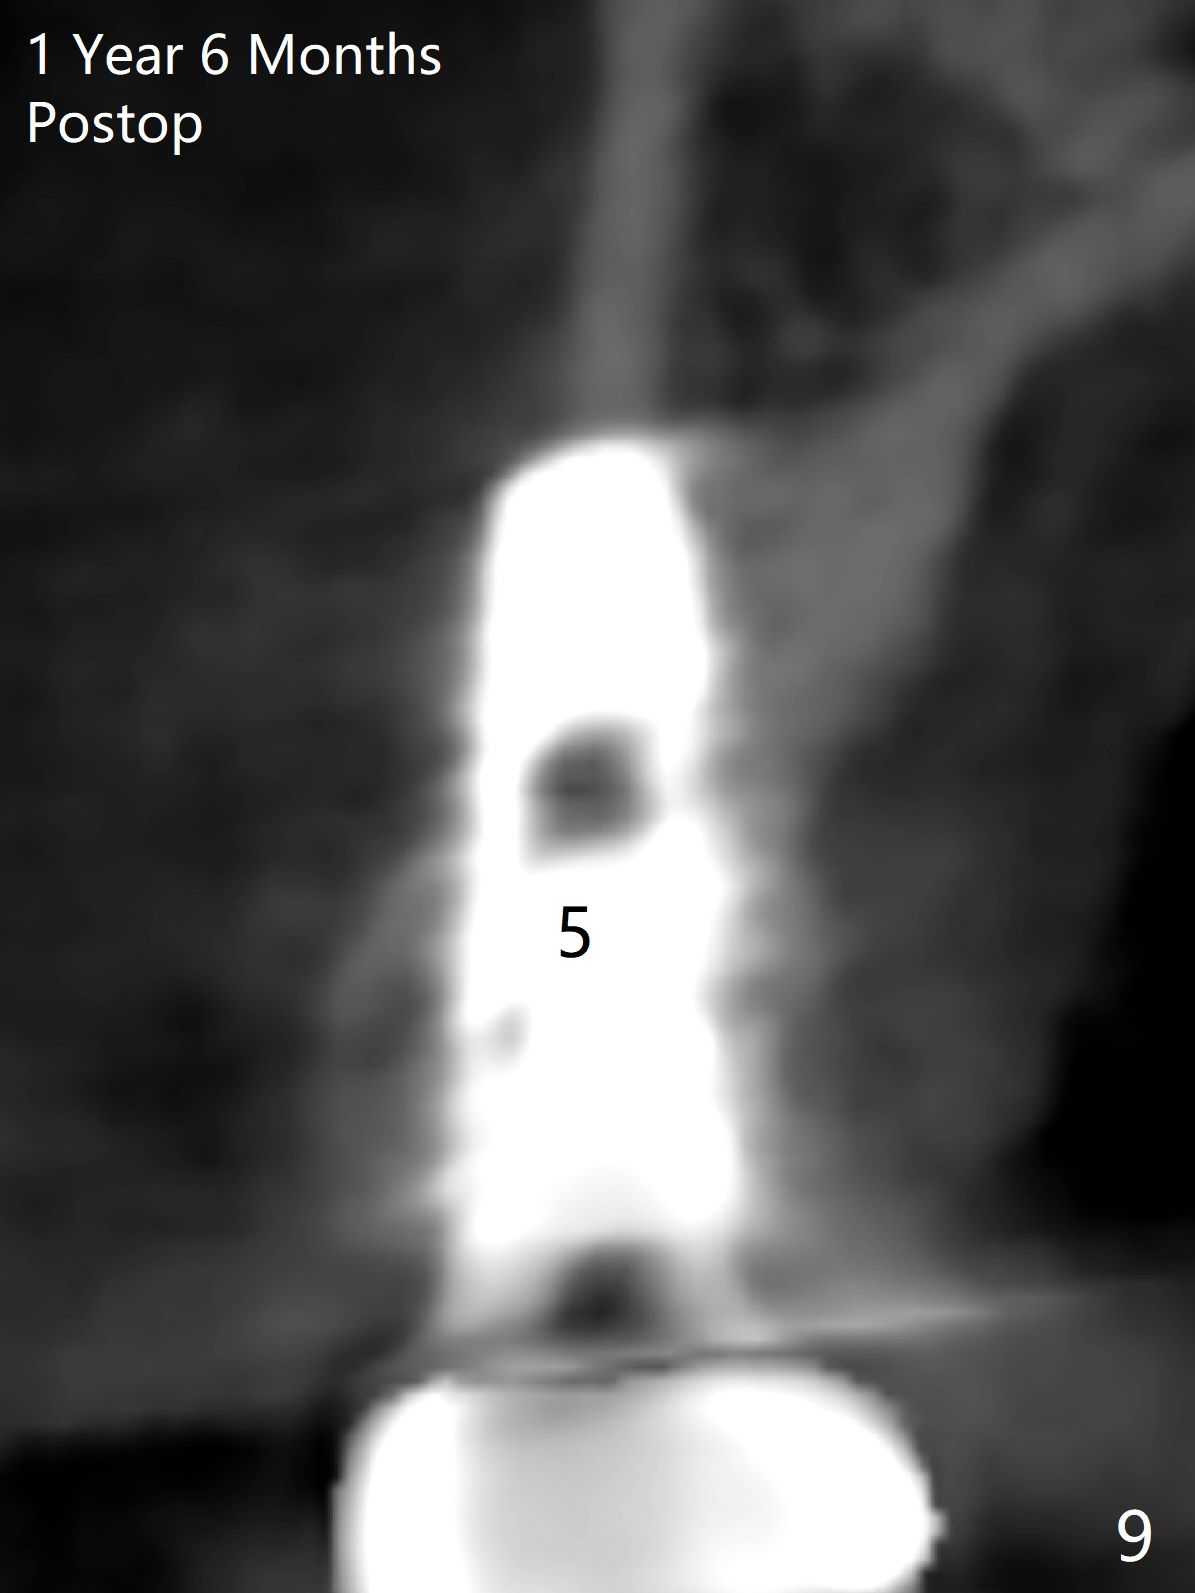

The buccal plate of the socket of #4 is thin and short (Fig.1, 5B (coronal section of the socket) red area) with apical perforation (Fig.5B >). Osteotomy at #4 starts with 1.6 mm drill in the palatal slope (Fig.2 circle; Fig.5C blue arrow), while that at #5 with Magic Split (Fig.2 black line). In fact sinus perforation occurs with the 1.6 mm drill. Osteotomy increases by using Magic Drills sequentially (2.8 and 3.3 mm) at #4 and Magic expander (3.0 mm) and the same Magic Drills at #5 (Fig.3). A 4x11 mm dummy IBS implant is placed with insertion torque of 45 Ncm at #4 with apparently intruding into the sinus (Fig.3). When a 4.5x9 mm implant is placed, the insertion torque is actually reduced (<35 Ncm, Fig.4). As osteotomy or implant diameter enlarges, it shifts buccally with less bone contact buccally (Fig.5D, as compared to Fig.5C)). In brief, once a dummy implant has achieved a reasonably high stability, do not over seat it. A small immediate implant may have more solid bone contact.

At the healed site (#5), insertion torque of a 4x11 mm implant is >50 Ncm (Fig.4). Because of supraeruption of the tooth #28 (Fig.6 arrow), a healing abutment (4x2 mm) is placed at #5 (data not shown), while a pair abutment (4.5x4(2) mm) is placed at #4 (Fig.4,6). In fact a splinted provisional is placed at #4 and 5 with a low occlusal table. There is no apparent bone loss 1 years 5 months postop (Fig.7). In fact the implants either perforate the palaatal or buccal (B) plate, as revealed by CBCT (1 year 6 months postop, immediately post cementation, Fig.8,9). It appears necessary to have guided surgery and smaller implant in the narrow ridge.